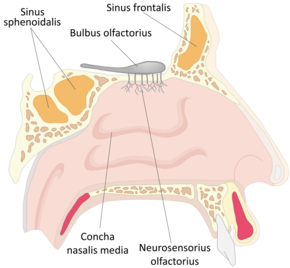

Internal anatomy of the nose | |

The bony part of the nasal septum is composed of the vomer bone (the lower part of the nasal septum), the perpendicular plate, (the upper part of the septum), aspects of the premaxilla, and the palatine bones. Each lateral nasal wall contains three nasal conchae, (also called turbinates) which are small, thin, shell-form bones: (i) the superior concha, (ii) the middle concha, and (iii) the inferior concha. Lateral to the conchae is the medial wall of the maxillary sinus. Inferior to each nasal concha is a nasal meatus, with names that correspond to the conchae, as superior meatus, middle meatus and inferior meatus. The internal roof of the nose is composed by the horizontal, perforated cribriform plate (of the ethmoid bone) through which pass sensory fibers of the olfactory nerve (CN1); finally, below and behind (posteroinferior) the cribriform plate, sloping down at an angle, is the bony face of the sphenoidal sinus.

Internal nasal anatomy

In the midline of the nose, the septum is a composite (bony-cartilaginous) structure that divides the nose into two similar halves. The lateral nasal wall and the paranasal sinuses, the superior concha, the middle concha, and the inferior concha, form the corresponding passages, the superior meatus, the middle meatus, and the inferior meatus, on the lateral nasal wall. The superior meatus is the drainage area for the posterior ethmoid bone cells and the sphenoid sinus; the middle meatus provides drainage for the anterior ethmoid sinuses and for the maxillary and frontal sinuses; and the inferior meatus provides drainage for the nasolacrimal duct.

The internal nasal valve comprises the area bounded by the upper lateral-cartilage, the septum, the nasal floor, and the anterior head of the inferior turbinate. In the narrow (leptorrhine) nose, this is the narrowest portion of the nasal airway. Generally, this area requires an angle greater than 15 degrees for unobstructed breathing; for the correction of such narrowness, the width of the nasal valve can be increased with spreader grafts and flaring sutures.